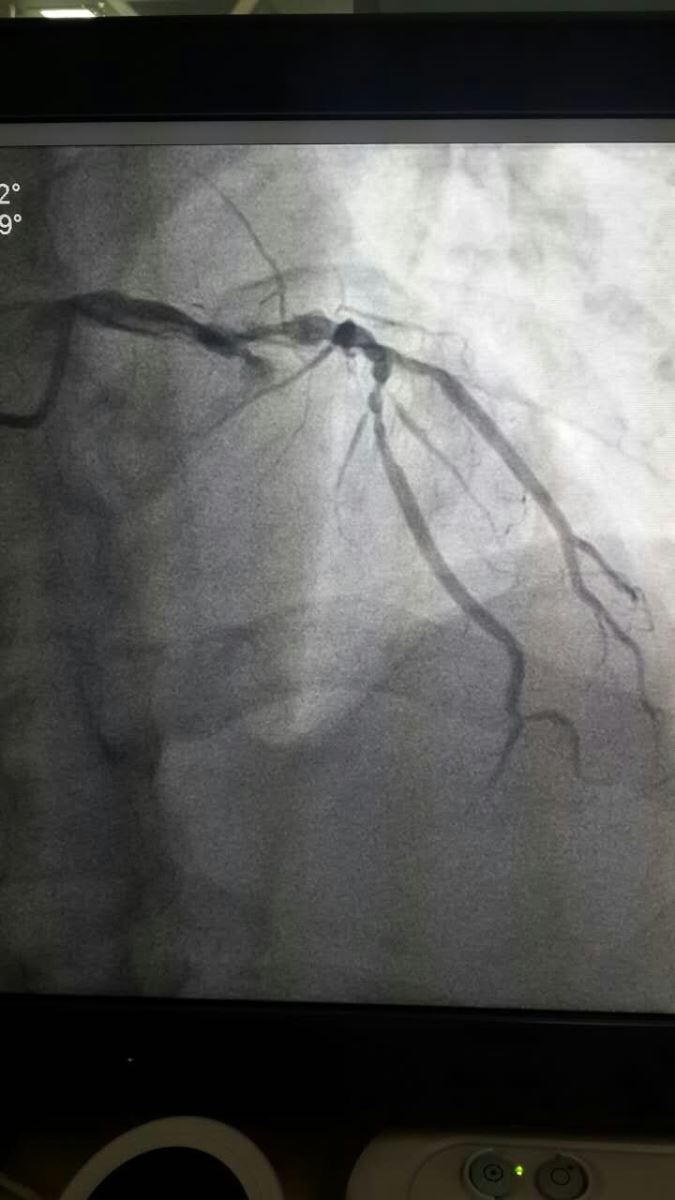

无影灯亮起,医生们站上手术台,一场没有硝烟的战争就此打响。我院心血管内一科介入医生立即展开手术。术前患者情况急转直下,血压降至60/40mmHg,心率降至40次/分,心电监护示频发室性早搏,迅速完成冠状动脉造影检查,发现左冠前降支近段近开口处完全闭塞伴有血管瘤及瘤样扩张,左回旋支多发瘤样扩张、管腔最重处达85%狭窄,手术风险极大,与陪同人员及与家属电话多次沟通后,在前降支球囊扩张后植入药物支架一枚,血管再通,前向血流恢复3级。在胸痛中心医护人员的努力下,为患者最快速度开通了“罪犯”血管,使患者转危为安,安返病室。手术仅45分钟(含与家属沟通时间),而D-to-B(进医院大门至首次球囊扩张)时间由之前台均约240分钟缩短至93分钟,执行先救治、后收费使得疾病及时救治,没有延误。我院胸痛中心再传捷报,绿色通道为拯救生命争得了时间。

手术前 手术后